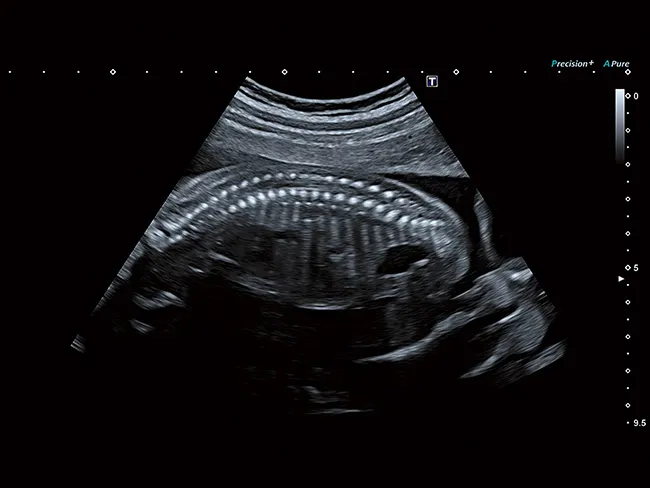

Тонкие конвексные датчики Aplio идеально подходят для межреберного сканирования. Новая насадка для биопсии с минимальной слепой зоной и возможностью выбора угла пункции обеспечивает оптимальные условия пункции для каждого пациента.